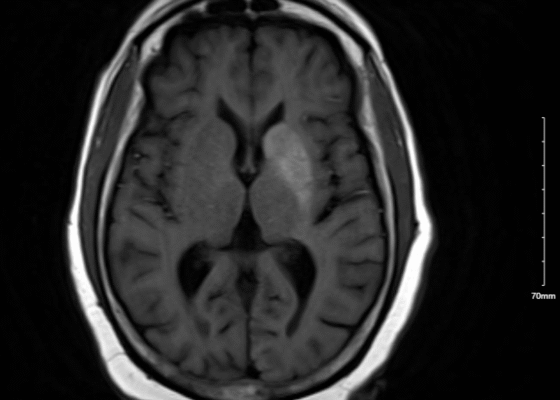

DOI: https://doi.org/10.21980/J8.52115Laboratory tests indicated elevated blood glucose levels (198 mg/dL) with no urinary ketones, anion gap of 12, thyroid stimulating hormone (TSH) of 12 UIU/ml, and an increased glycated hemoglobin (HbA1c) of 14.9%. After initial stroke evaluation with neurology, imaging studies, including computed tomography (CT)/CT angiography (CTA) of the brain and neck, were unremarkable, ruling out structural lesions or acute stroke. Neurology recommended an MRI which showed T1 shortening within the left basal ganglia involving both the caudate nucleus and the lentiform nucleus. T1 shortening indicates changes in the tissue composition or structure that alters how the tissue responds to the MRI pulse, giving the tissue a brighter appearance on MRI (see white arrow).